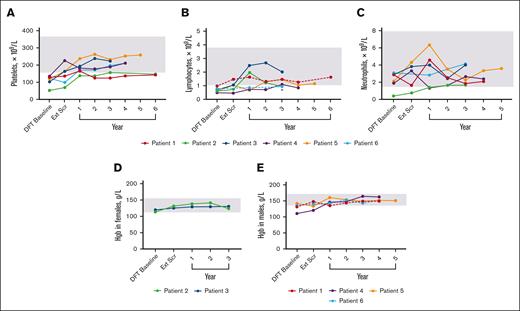

Laboratory values were used to determine the presence of cytopenias (Figure 6). Histories included thrombocytopenia (n = 6), lymphopenia (n = 4), neutropenia (n = 1), and anemia (n = 1). By the end of the DFT, 3 lymphopenia and 3 thrombocytopenia cases resolved. During continued treatment, 4 patients presented with cytopenias that included thrombocytopenia (n = 3), neutropenia (n = 1), anemia (n = 1), and lymphopenia (n = 2). At the latest time with available data, the neutropenia and anemia case resolved, whereas thrombocytopenia improved in 2 patients and resolved in 1 around year 1. Both lymphopenia cases improved but persist.

Changes in hematologic parameters over time. (A) Platelet levels for individual patients over time. n values for DFT baseline, Ext Scr, and years 1, 2, 3, 4, 5, and 6 are as follows: 6, 6, 6, 6, 6, 4, 1, and 2, respectively. There was no reported value at year 3 for P3; data from year 3.5 of treatment was used. (B) Lymphocyte levels for individual patients over time. n value for DFT baseline, Ext Scr, and years 1, 2, 3, 4, 5, and 6 are as follows: 6, 5, 6, 5, 6, 3, 1, and 1, respectively. P1 and P6 (dashed lines) were the only patients within range at the DFT. Asterisk denotes the latest time point for P6 that exceeded their individual lower limit of 0.5 × 109/L. (C) Neutrophil levels for individual patients over time. n values for DFT baseline, Ext Scr, and years 1, 2, 3, 4, and 5 are as follows: 6, 5, 6, 5, 6, 3, and 1, respectively. For lymphocytes and neutrophils, there was no reported value at year 3 or 1 for P3 and P1, respectively; data from year 3.5 and 0.5, respectively, were used. (D) Hemoglobin levels over time for individual female patients. n values for all time points are 2. There was no reported value at year 3 for P3; data from year 3.5 of treatment was used. (E) Hemoglobin levels over time for individual male patients. n values for DFT baseline, Ext Scr, and years 1, 2, 3, 4, and 5 are as follows: 4, 4, 4, 4, 4, 4, and 1, respectively. P1 and P6 (dashed lines) were the only patients within range at DFT baseline. Gray boxes indicate mean normal range that was determined by averaging lower and upper limit for all 6 patients (panels A-C), female patients only (panel D), or male patients only (panel E). Hgb, hemoglobin.

Changes in hematologic parameters over time. (A) Platelet levels for individual patients over time. n values for DFT baseline, Ext Scr, and years 1, 2, 3, 4, 5, and 6 are as follows: 6, 6, 6, 6, 6, 4, 1, and 2, respectively. There was no reported value at year 3 for P3; data from year 3.5 of treatment was used. (B) Lymphocyte levels for individual patients over time. n value for DFT baseline, Ext Scr, and years 1, 2, 3, 4, 5, and 6 are as follows: 6, 5, 6, 5, 6, 3, 1, and 1, respectively. P1 and P6 (dashed lines) were the only patients within range at the DFT. Asterisk denotes the latest time point for P6 that exceeded their individual lower limit of 0.5 × 109/L. (C) Neutrophil levels for individual patients over time. n values for DFT baseline, Ext Scr, and years 1, 2, 3, 4, and 5 are as follows: 6, 5, 6, 5, 6, 3, and 1, respectively. For lymphocytes and neutrophils, there was no reported value at year 3 or 1 for P3 and P1, respectively; data from year 3.5 and 0.5, respectively, were used. (D) Hemoglobin levels over time for individual female patients. n values for all time points are 2. There was no reported value at year 3 for P3; data from year 3.5 of treatment was used. (E) Hemoglobin levels over time for individual male patients. n values for DFT baseline, Ext Scr, and years 1, 2, 3, 4, and 5 are as follows: 4, 4, 4, 4, 4, 4, and 1, respectively. P1 and P6 (dashed lines) were the only patients within range at DFT baseline. Gray boxes indicate mean normal range that was determined by averaging lower and upper limit for all 6 patients (panels A-C), female patients only (panel D), or male patients only (panel E). Hgb, hemoglobin.